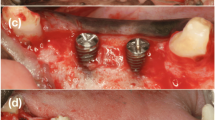

After 12 weeks, the fenestration defects were created in a second experimental phase. For this, vertical releasing incisions were made in the gingiva, and the mucoperiosteal flap was elevated to expose the mandibular bone. The appropriate implant placement sites were chosen, and the bone was prepared per the implant’s drilling sequence. Defects 3.3 mm wide and 6.0 mm high were created by drilling the buccal wall of the selected site, exposing the implant surface. The implants (BL NC 3.3 × 8 mm, Straumann, Madrid, Spain) were placed, and the defects were filled with either the test material (TP), the control material (ABB) or left empty (unfilled defect), and in all cases, a Bio-Gide® (Geistlich Bio-Gide®, INIBSA, Barcelona, Spain) membrane was used (Fig. 1). The fenestrations were covered with the membrane, ensuring that they were immobilized. When necessary, they were immobilized by osteosynthesis pins. Mucoperiosteal flaps were then sutured with Supramid 5/0 (Aragó, Barcelona, Spain) obtaining primary closure (Fig. 1). After this surgery, the animals were allowed to heal for 12 weeks. A postoperative antibiotic regimen (cefovecin sodium 8 mg/kg/s.i.d./s.c.; Convenia, Zoetis, Spain) was applied to avoid infection.

Intra-operative views. a initial, b flap design, c implant placement and defects generation, d defects were implanted with Bio-Oss®, Sil-Oss® or no biomaterial, e each defect area was covered with a porcine-derived collagen barrier membrane (BioGide®), f flaps were repositioned and primary wound closure was achieved